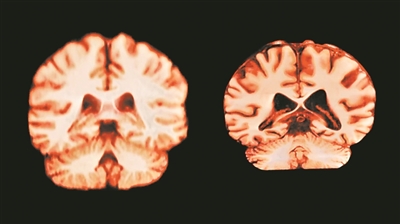

健康大脑(左)和受阿尔茨海默病影响的大脑。

图片来源:英国《自然》杂志网站

了解健康大脑的自然老化规律,有助于更好地认识神经退行性疾病的发展机制。若阿尔茨海默病与这些变化相关,应当能在女性的海马体和楔前叶等关键区域中观察到更快的萎缩,但研究未发现这种现象。阿尔茨海默病的成因复杂,仅凭年龄相关的脑萎缩不足以揭示其机制。